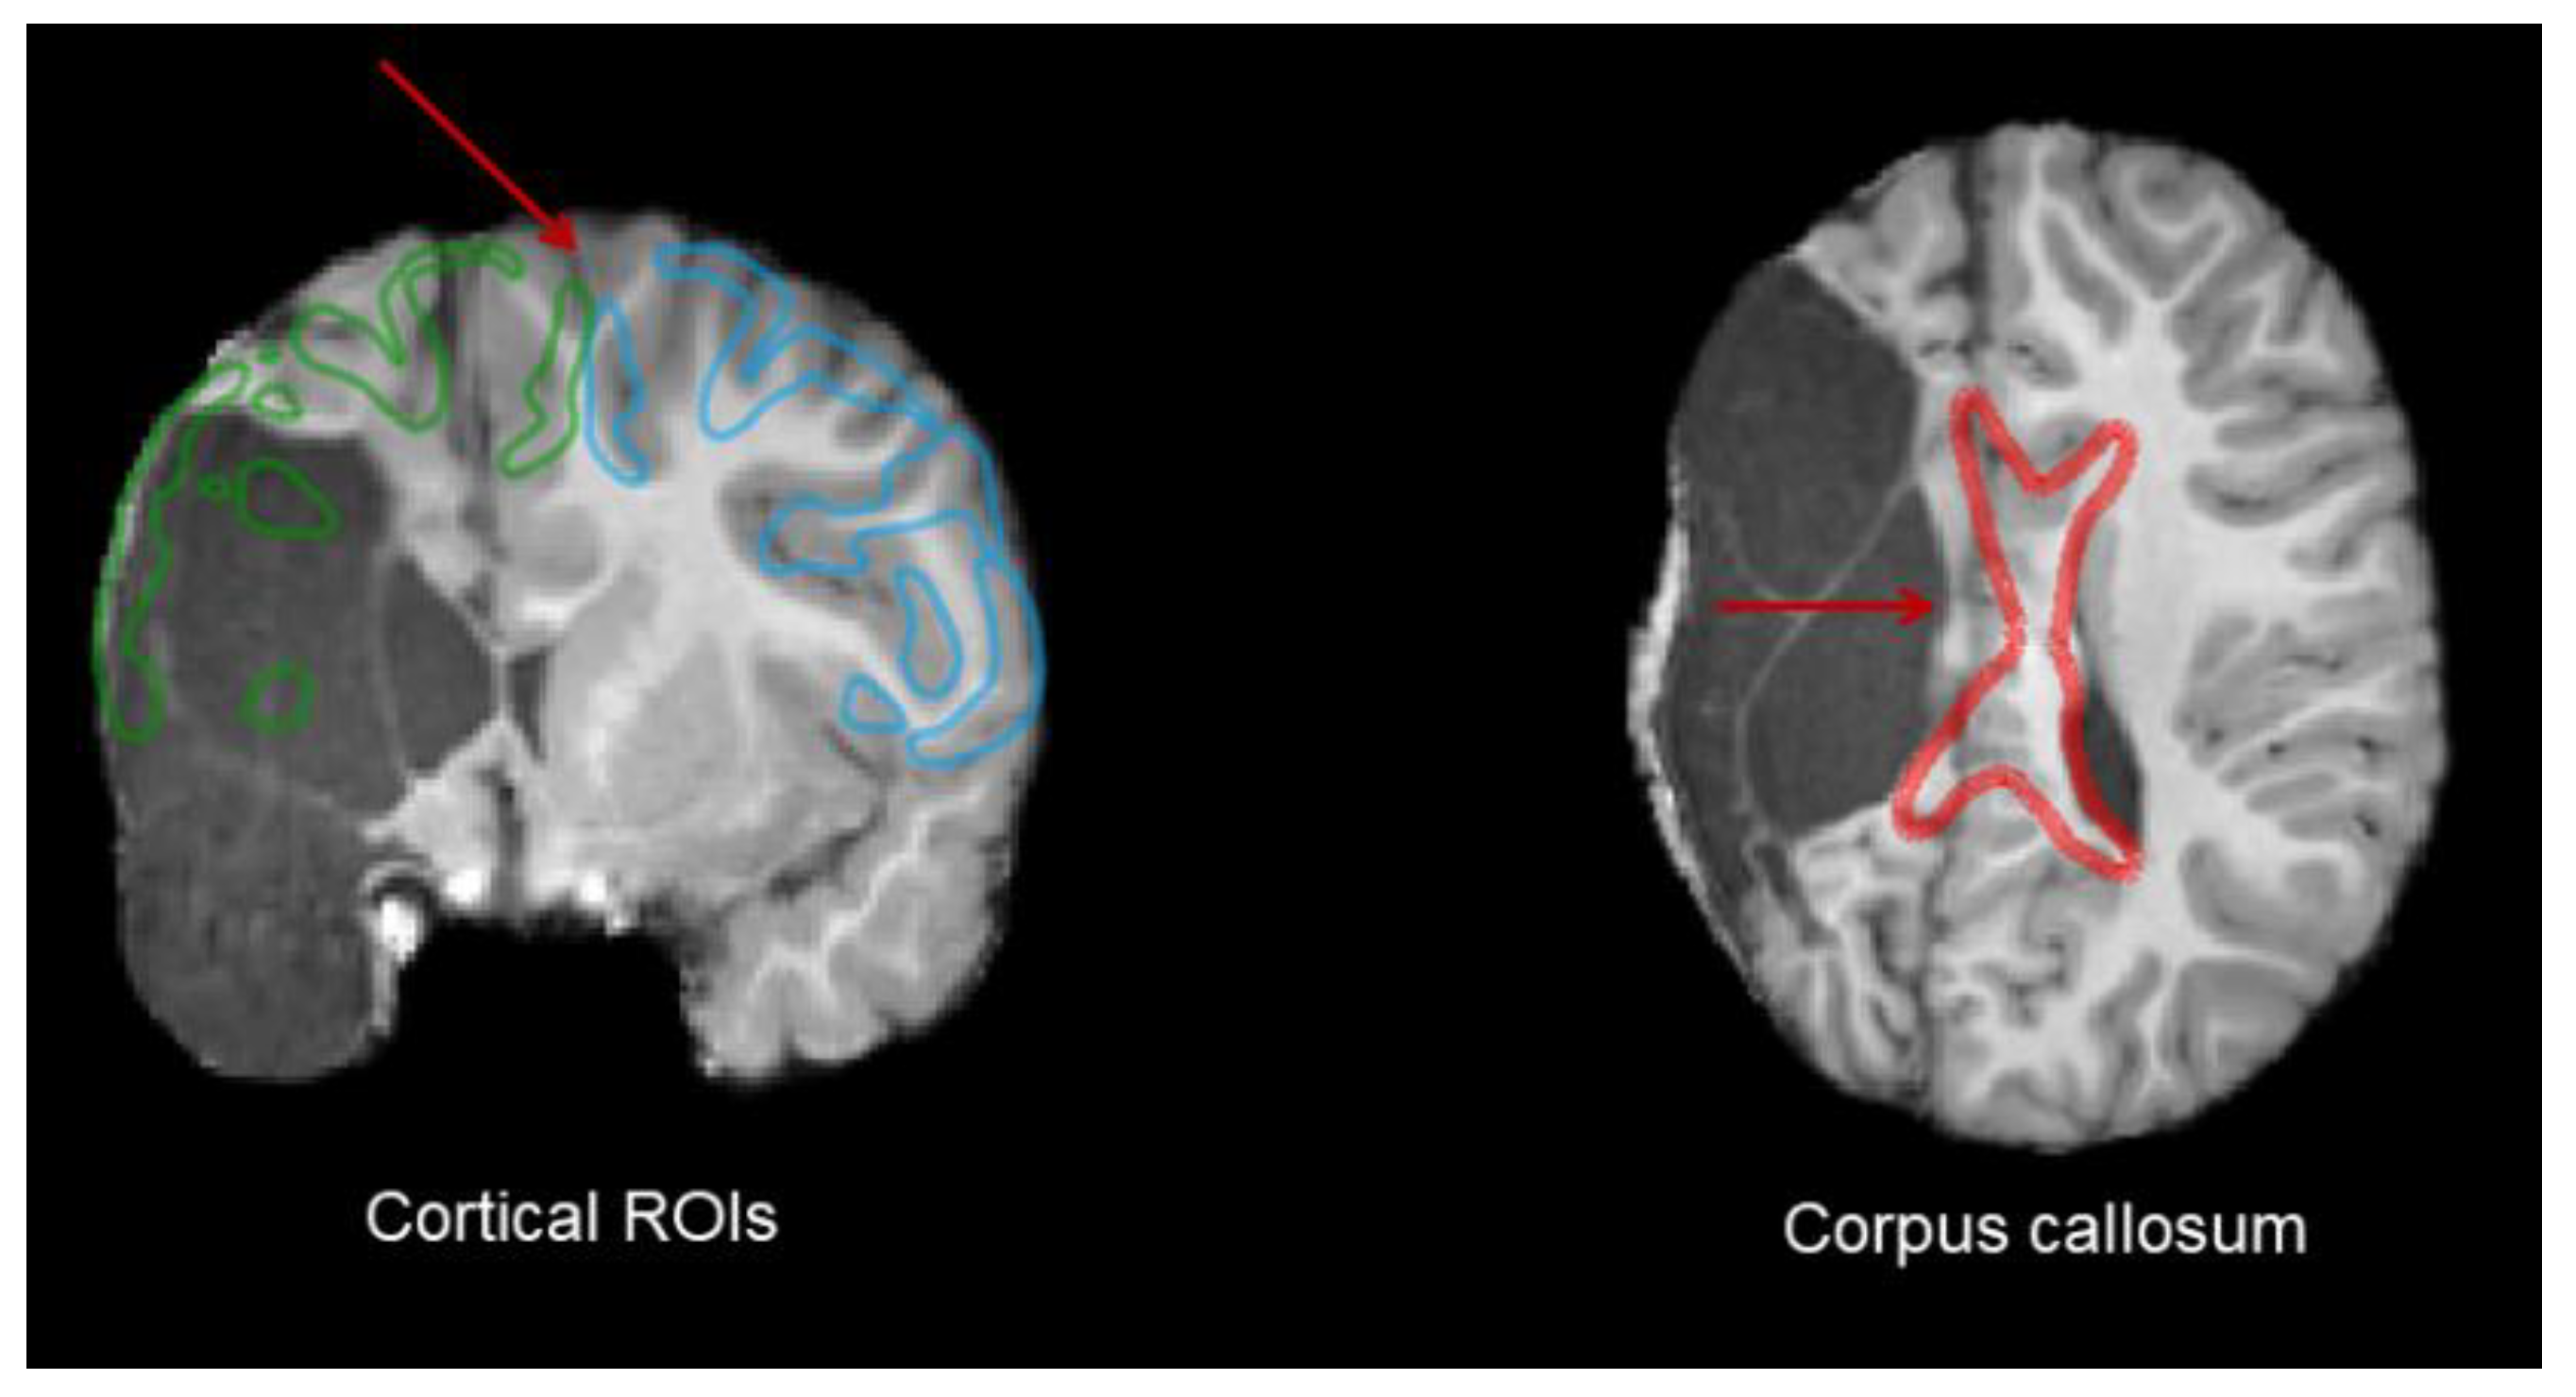

Atlas-Based Customized Extraction

- ROI and Bundle Extraction

3.2.2. Corpus Callosum